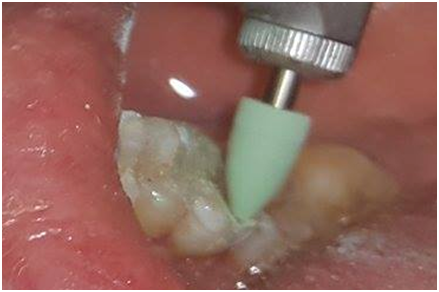

On the buccal surface of the restoration, the margins were located 0.5mm sub-gingivally for esthetic reasons and supra-gingivally on the lingual side. All sharp edges were rounded and smoothed (Figure 3). After a double gingival cord retraction, a simultaneous double mixed impression was made using light and heavy silicon A (Figure 4).

Figures 3 Tooth preparation.

After elimination of the amalgam the molar was prepared respecting the preparation guidelines for ceramic inlays/onlays.4

1. The angles between the floor and the axial walls had to be rounded.

2. The divergence of the internal walls should not be too limited (≥10°).

3. The cavo-superficial boundaries shall be sharp, without bevel.

4. Occlusal areas should not be located at the tooth restoration interface.

5. The width of the main isthmus should be ≥

6. The proximal box had to have a mesio-distal width of at least 1mm.

7. The thickness of the restoration had to be of the order of 2mm at the level of the occlusal groove.

8. The width of the residual walls had to be at least 2mm at the cervical level and 1 mm at the occlusal level.

9. The thickness of the restorative materials (composite or ceramic) should be at least 1.5 to 2mm at the level of the covered cusps.

10. A rounded shoulder is recommended at the level of the covered cusps.